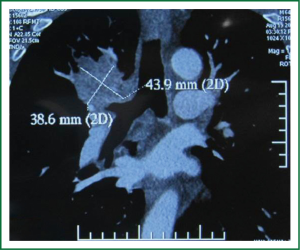

The patient was a 66-year-old male, who was admitted into our hospital due to coughing and blood-tainted sputum for over a month. He had a history of hypertension for 4 years, and a long history of heavy smoking, with a smoking index over 1,000 pack years. A chest CT scan, performed in other hospital on 10 August 2012, suggested a right upper lobe mass. A fibrous bronchoscopy, performed in our hospital on August 13, 2013, showed a neoplasm at the opening of the right upper lobe bronchus, blocking part of the bronchus. A biopsy with pathology suggested squamous carcinoma. A chest CT scan with enhancement, which was performed in our hospital on August 19, 2013, showed a right upper lobe mass considered as a central lung cancer, without visible lymph nodes enlargement in the mediastinum (Figure 1). The patient’s preoperative routine examinations did not reveal significant surgical contraindication, and his lung function was basically within the normal range.